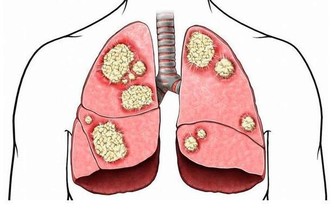

黃子慧說,乳腺結核病、乳腺癌患者經常會導致腋窩淋巴結腫大,

因此,如果是發現有腋窩淋巴結腫大,首先要排除這兩種病的可能。

另外如果出現無痛性腋窩淋巴結腫大,很可能是淋巴癌導致的。